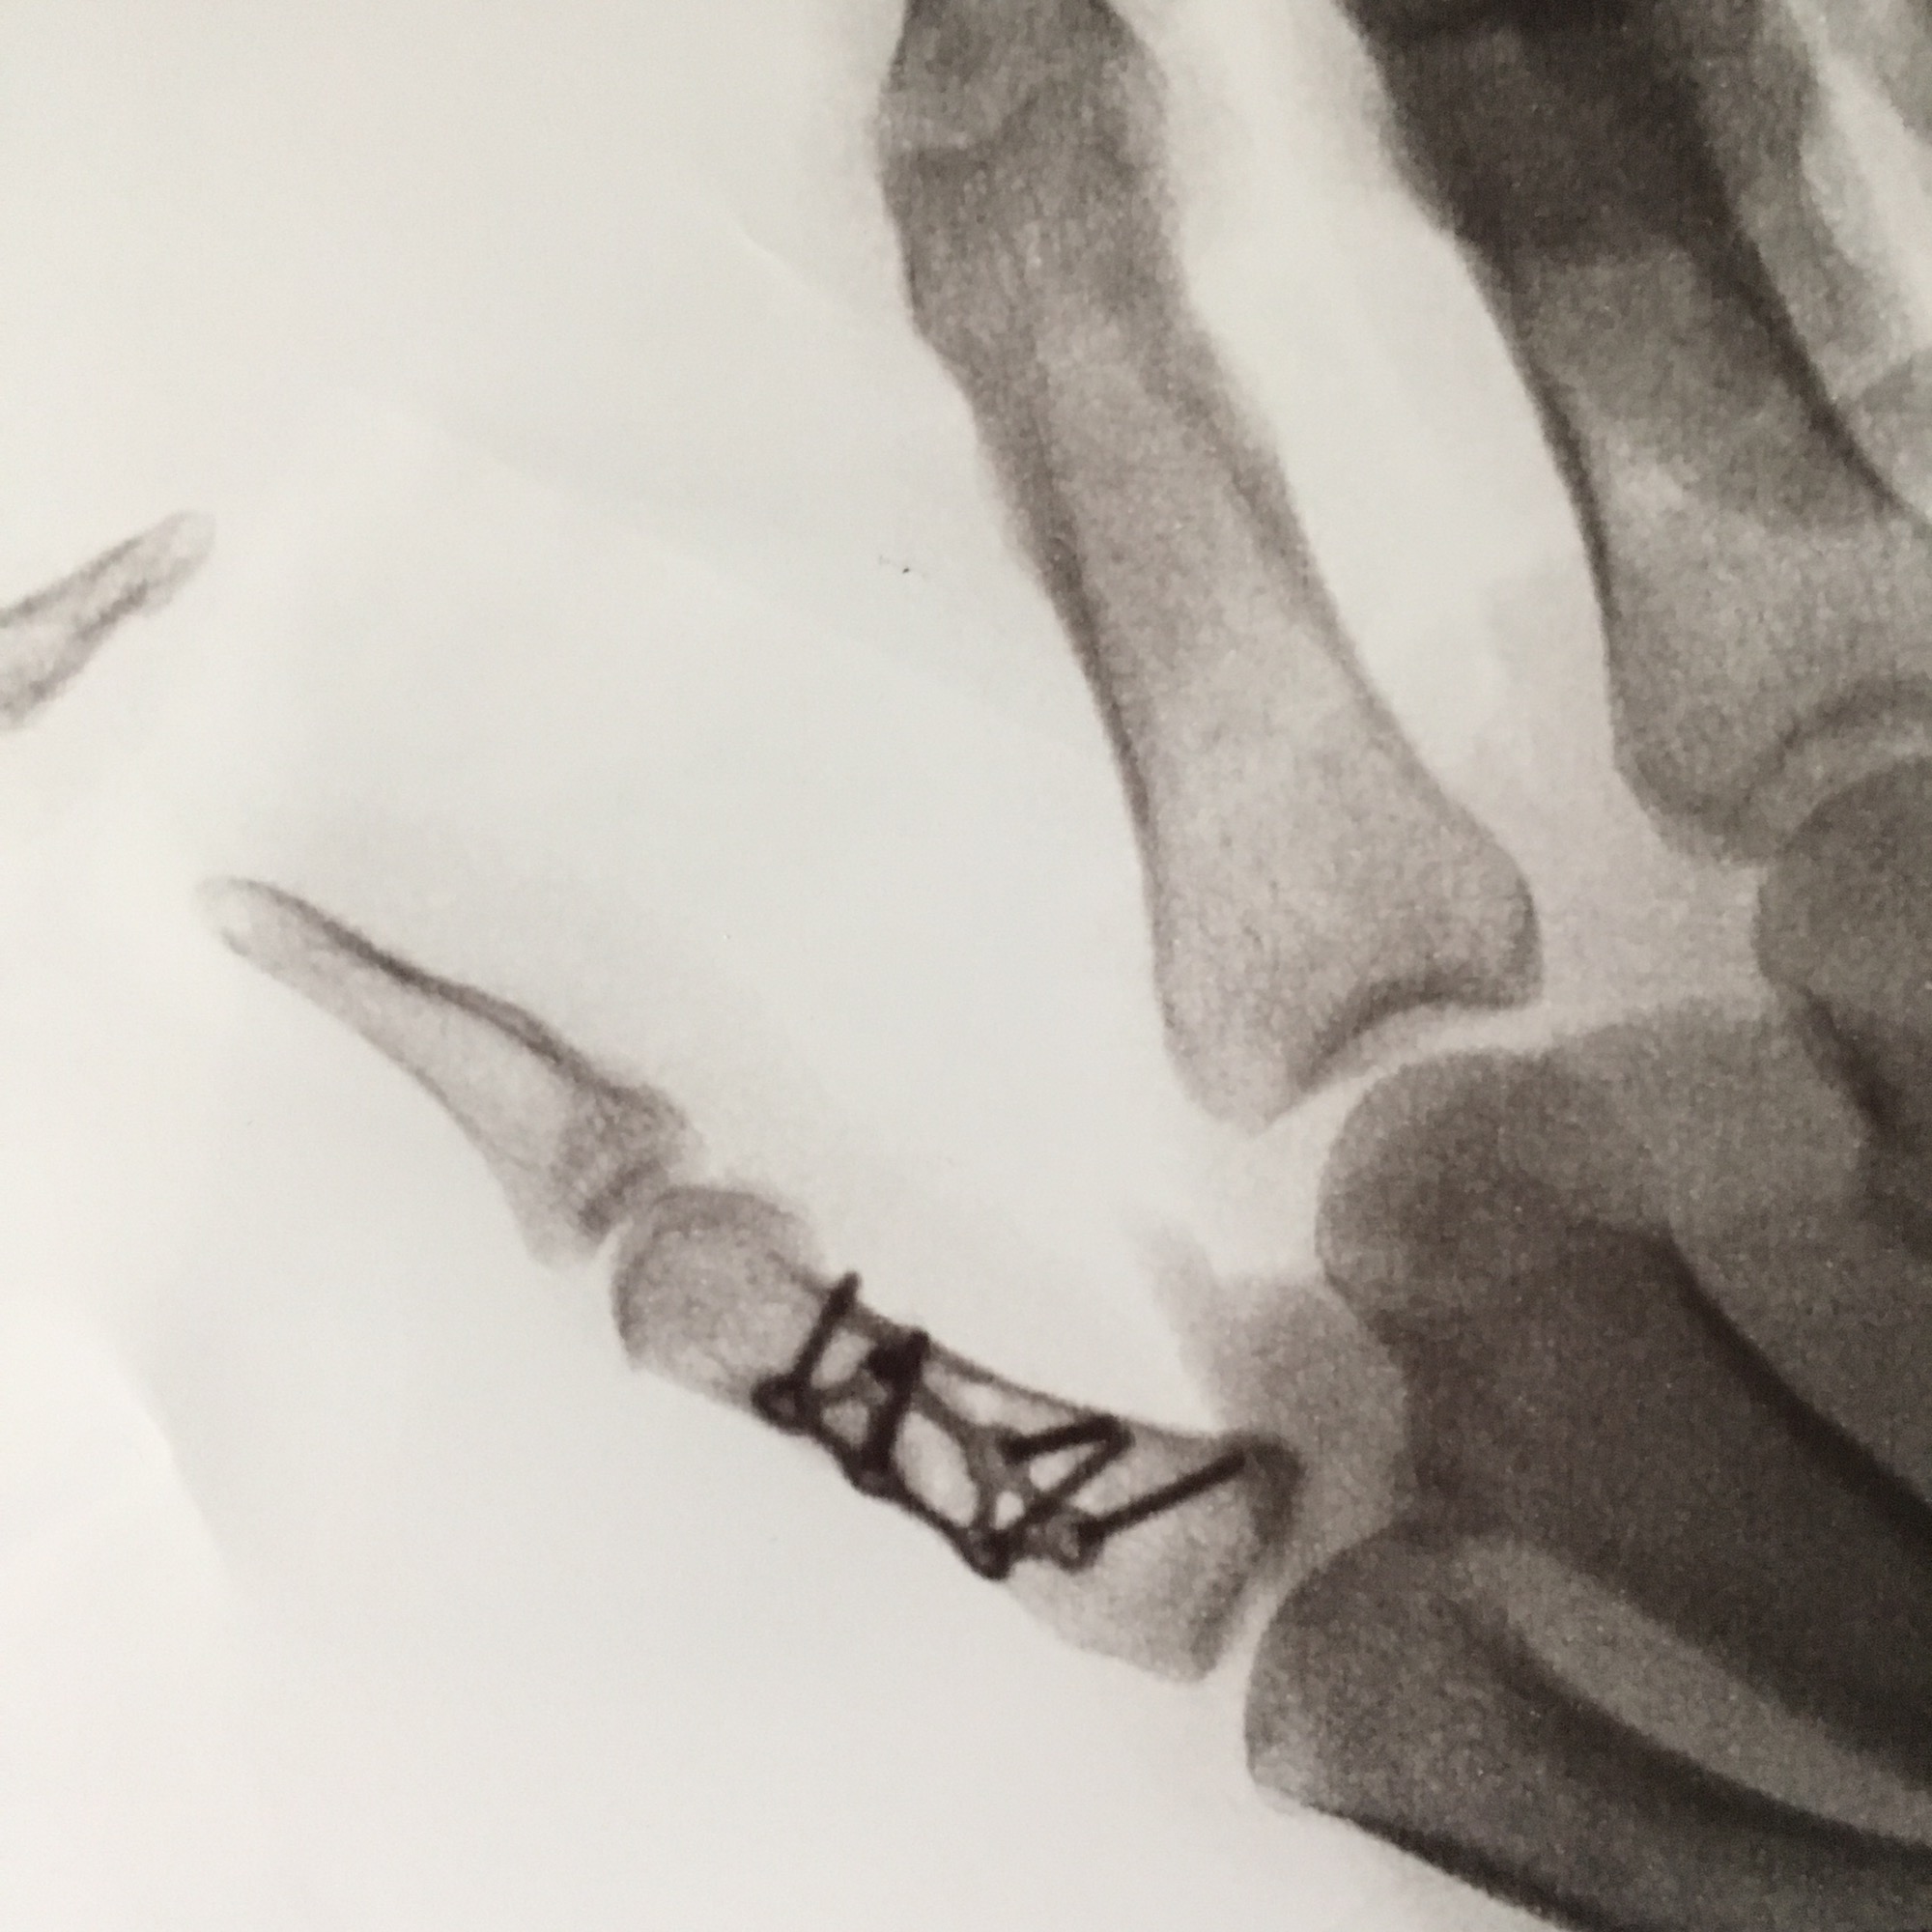

Along with my souvenir cast the real and very permanent additions I now have are a titanium plate held in place with 6 (1.5 mm diameter) titanium screws. Having spent a good deal of time in my past careers playing with metals I know that my new addictions will out late me by many lifetimes. As we used to say years ago about titanium “it will never lose it shape, color, texture, or rust, rot, warp, fade in any way….ever”. In other words there here to stay.

Looking from the palm side.

Looking the other way.